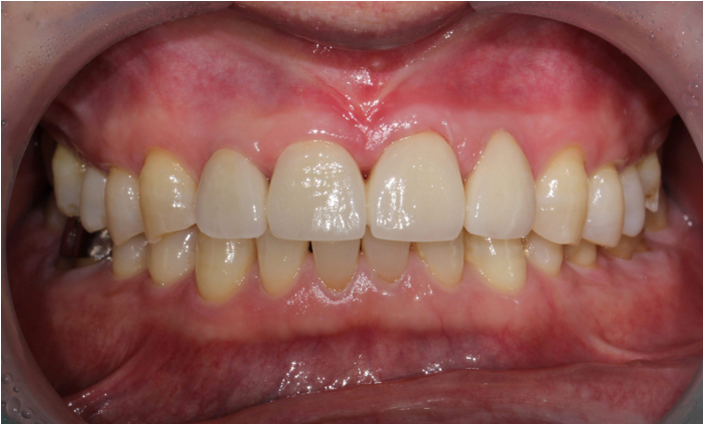

앞니 심미보철 셋팅 완료

장기적으로 전치부 교합이 심해 마모가 심한 치아의 경우에는 라미네이트보단

전체 크라운 치료가 파절 가능성을 낮추고 치아 사이 벌어짐을 막을 수 있어서 좋은 치료 방법으로 고려됩니다 ^^